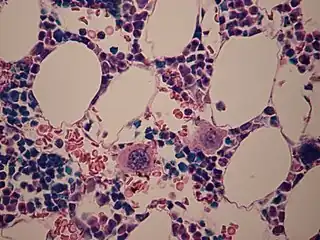

Se observan dos megacariocitos (un poco por debajo del centro) en una muestra de médula ósea.

Los megacariocitos (del griego μεγας (megas = grande) + καριον (carion = núcleo) + κυτος (cytos = célula) (célula gigante multilobulada) son unas células muy conspicuas que forman parte del tejido hematopoyético de la médula ósea y de otros tejidos hematopoyéticos. Se trata de una célula muy grande (mide unos 30 μm de diámetro), poliploide y polinucleadas, con numerosas ramificaciones.[1]